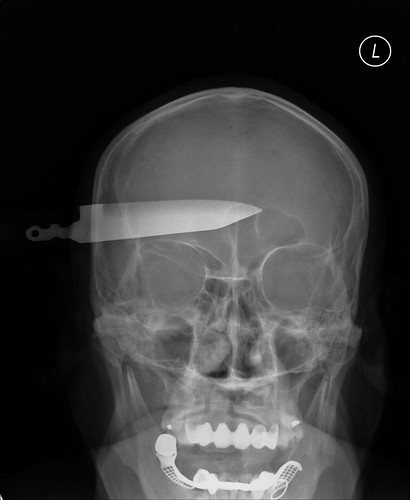

If these knives can do it, a high end combat weapon like the TGLB would have NO TROUBLE doing it

tumblr_l29zzl6jxy1qza0fjo1_500_thumb.jpg